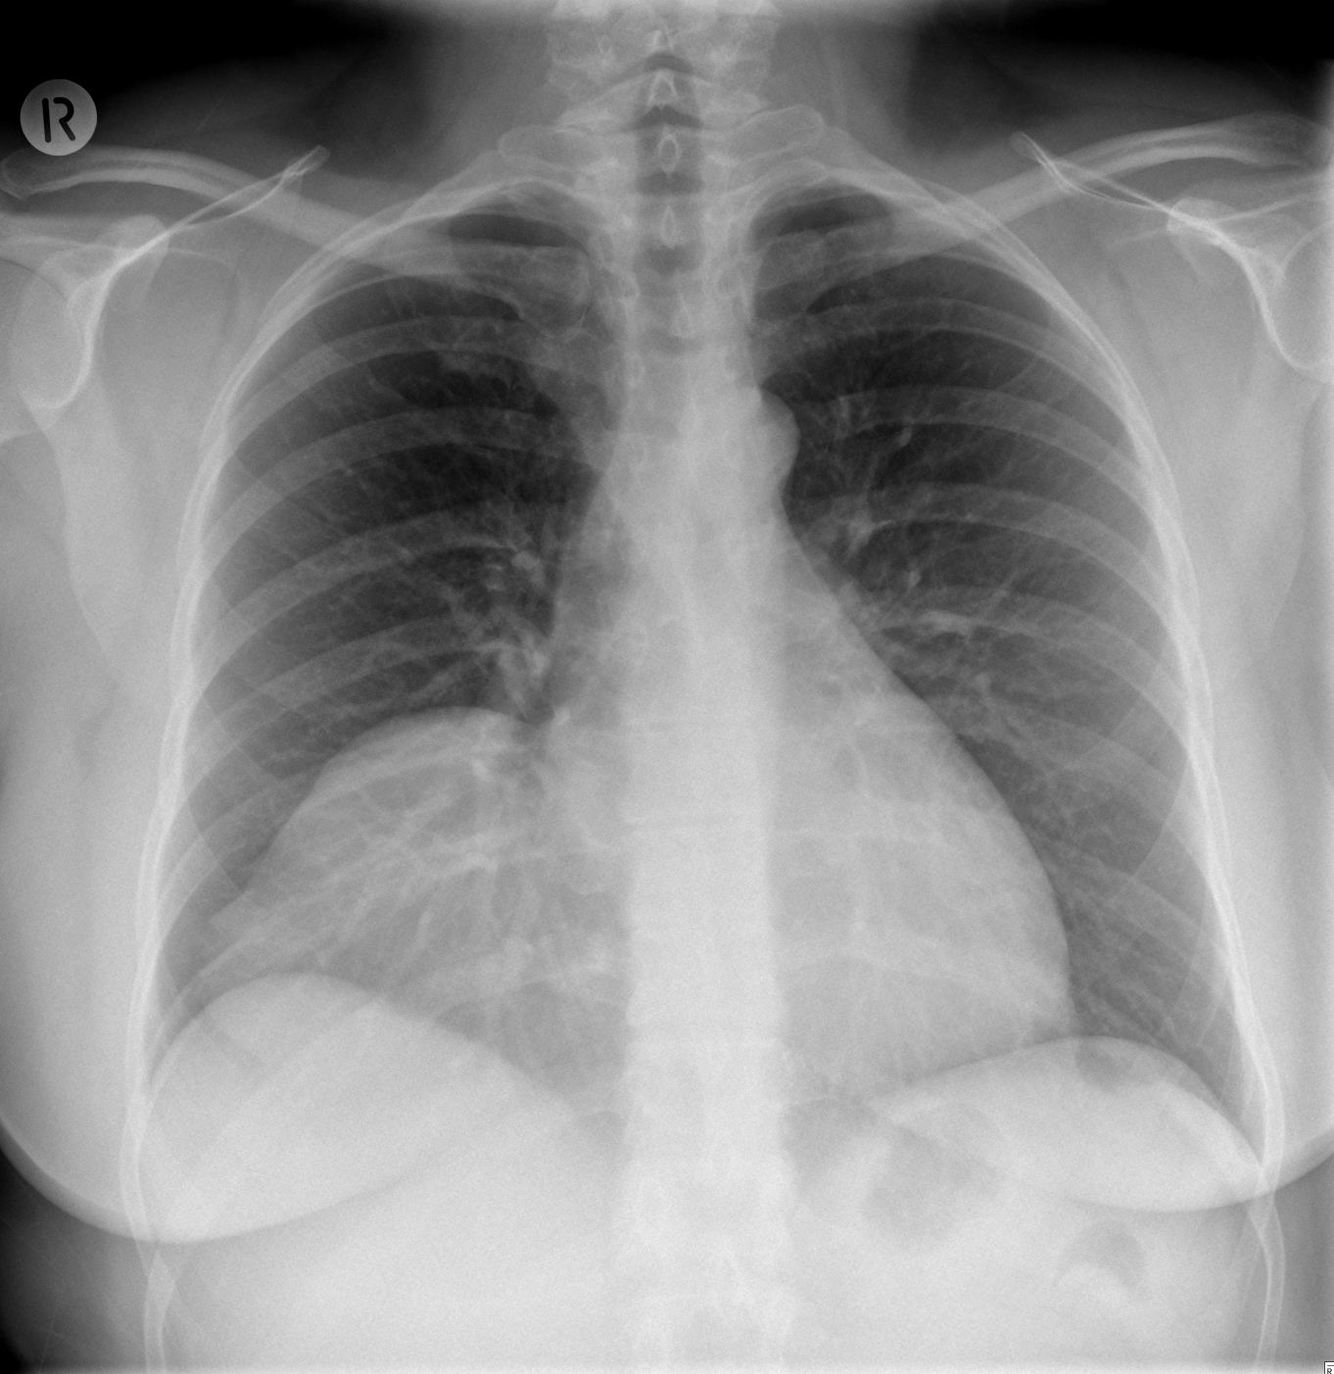

Pericardial agenesis (partial) is a rare cardiac defect. Radiologically, it presents with the following :

levoposition of the heart

prominent pulmonary artery

air interface in the aorto-pulmonary window or between the base of the heart and the diapgragm

CT-scan is better than MRI for this diagnosis, since it has better spatial resolution. The pericardial defect will be seen. A complete pericardial defect is a benign condition, while patients with partial agenesis may have cardiac herniation through the defect. They should be managed surgically.